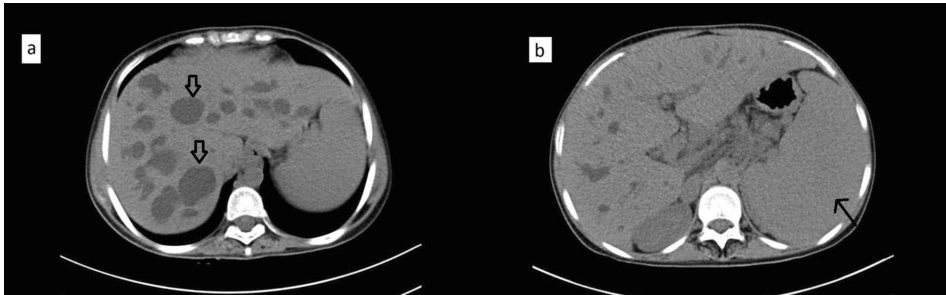

本刊推荐:为探讨脾动脉栓塞术(SAE)在Caroli综合征(CS)合并门静脉高压伴脾功能亢进患者中的治疗价值,研究人员开展病例研究。结果显示SAE可显著提升血小板计数(从29,000/μL升至394,000/μL),但术后出现发热、白细胞升高(WBC 19,000/μL)等栓塞后综合征。该研究为晚期Caroli综合征的并发症治疗提供了新思路,强调早期肝移植的重要性。